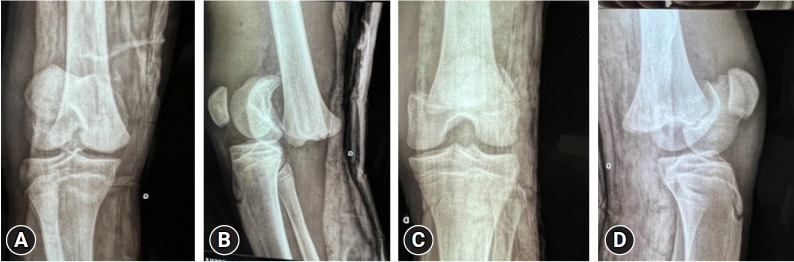

Epiphyseal dislocations and fractures frequently occur in children and adolescents. However, these injuries seldom involve the distal femur, and bilateral cases are even rarer. We present an unusual case of bilateral epiphyseal detachment of the femur in a 21-year-old man who was involved in a traffic accident. Open reduction and fixation surgery were performed 5 days after the incident. The patient experienced favorable progress, with consolidation occurring at 3 months. No lower limb length discrepancies were observed at the 20-month follow-up. In summary, bilateral distal femoral epiphyseal detachment is an uncommon condition that can be effectively treated through surgical intervention.